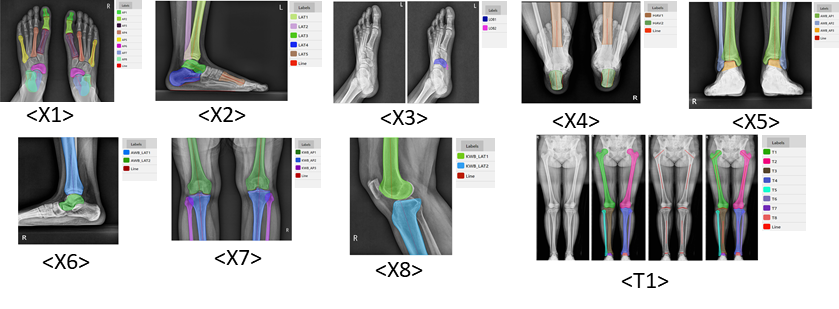

족부족관절 질환의 진단, 치료 모니터링을 위한 인공지능 학습용 멀티모달리티 DB 구축 – 영상자료 : 의료영상(X-Ray, Telegram), EOS, 보행분석, 보행동영상 – 영상 외 임상자료 : 인구학적 정보, 진단명, 수술명

| 라벨링 유형 | 키포인트(동영상/이미지), 세그멘테이션(이미지) | 라벨링 형식 | JSON |

5. 카테고리별 데이터구축 예시